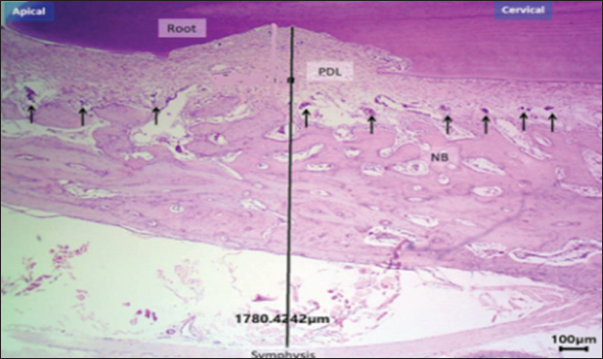

Histomorphometric analysis

Based on the histomorphometric findings, exogen treatment markedly enhanced bone-forming activity, as evidenced by a statistically significant increase in osteoblast count at both day 10 and 20 compared with the control group (p < 0.01), indicating accelerated bone formation. In contrast, osteoclast count was significantly reduced at day 20 (p < 0.05), reflecting suppression of bone resorption. Vascular density showed a consistent and significant increase across all post-removal time points (p < 0.01), providing a more favorable blood supply for bone and periodontal tissue healing. Additionally, PDL width was narrower in the Exogen group by day 20, suggesting enhanced tooth stability after orthodontic appliance removal. Representative histological sections at day 10 are shown in Figures 7 and 8.

Fig. 7. Histological section of the exogen-treated group at day 10 showing a broad zone of newly formed bone (NB) with aligned osteoblasts (arrows). H&E stain, 40×, scale bar=100 μm.

Fig. 8. Histological section at day 10 (non-Exogen group) showing multiple blood vessels (BV) within newly formed bone (NB). H&E stain, 40×, scale bar=100 μm.

This pattern of results translates into accelerated healing of bone and periodontal tissues with an improved vascular environment, supporting the hypothesis that LIPUS can reduce post-treatment tooth relapse and promote long-term stability (Fig. 9a and b). New bone surface distribution is demonstrated in Figure 10.

Fig. 9. Histological section of the control group at day 20 showing disorganized new bone (NB), widened PDL space, and multiple osteoclasts (arrows). H&E stain, 40×, scale bar=100 μm.

Fig. 10. H&E –stained sections representing new bone surface area in control and exogen groups along cervical and apical lines at day 0. H&E, 100×, scale bar=100 μm.